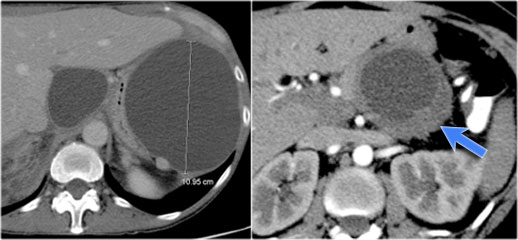

The CT demonstrates a large cyst in the upper abdomen in a patient who had an acute pancreatitis (Fig).

Notice that there is also some ascites and pleural fluid.

There is wall enhancement.

CT demonstrates two large cysts in a 45 year old woman, who had a trauma (fig).

Notice some fat stranding in the retroperitoneal space (arrow).

The imaging findings combined with the history make it very likely that these are traumatic pseudocysts.